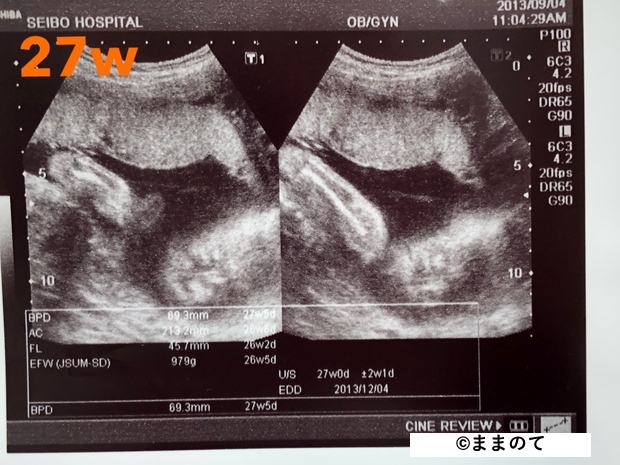

妊娠7ヶ月(24・25・26・27週)

赤ちゃんの器官が成熟し始め、耳が聞こえるようになってきます。そのため、人間らしい仕草をしたり、音に驚いたりするようになります。

身長は約35cm、体重は約1,000gになります。赤ちゃんの大きさが3Dエコーの撮影に最も適している時期で、タイミングが良ければ指しゃぶりやあくびをしている様子が見られるかもしれません。